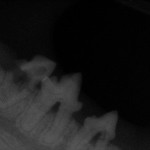

40% kotów cierpi na FORL czyli Feline Odontoclastic Resorptive Lesion. W rutynowym badaniu jamy ustnej choroba ta bardzo często nie daje żadnych objawów.

Najczęściej zaczyna się zwykle w wieku około 5 lat, nie jest to jednak reguła, mogą chorować zwierzęta starsze i młodsze. Ze względu na ekspozycję otwartych kanalików zębinowych oraz miazgi choroba jest bardzo bolesna. Najlepszą formą jej szybkiego diagnozowania jest wykonanie pełnego kompletu zdjęć rentgenowskich jamy ustnej. Każdy kot trafiający na zabieg stomatologiczny, niezależnie od przyczyny, ma wykonywane zdjęcia RTG wszystkich zębów. Cyfrowa radiografia wewnątrzustna pozwala nam to w zaledwie kilka minut uzyskać zdjęcia w doskonałej jakości, umożliwiające diagnozowanie wielu bolesnych problemów w jamie ustnej naszych podopiecznych i wdrożenie właściwego leczenia.